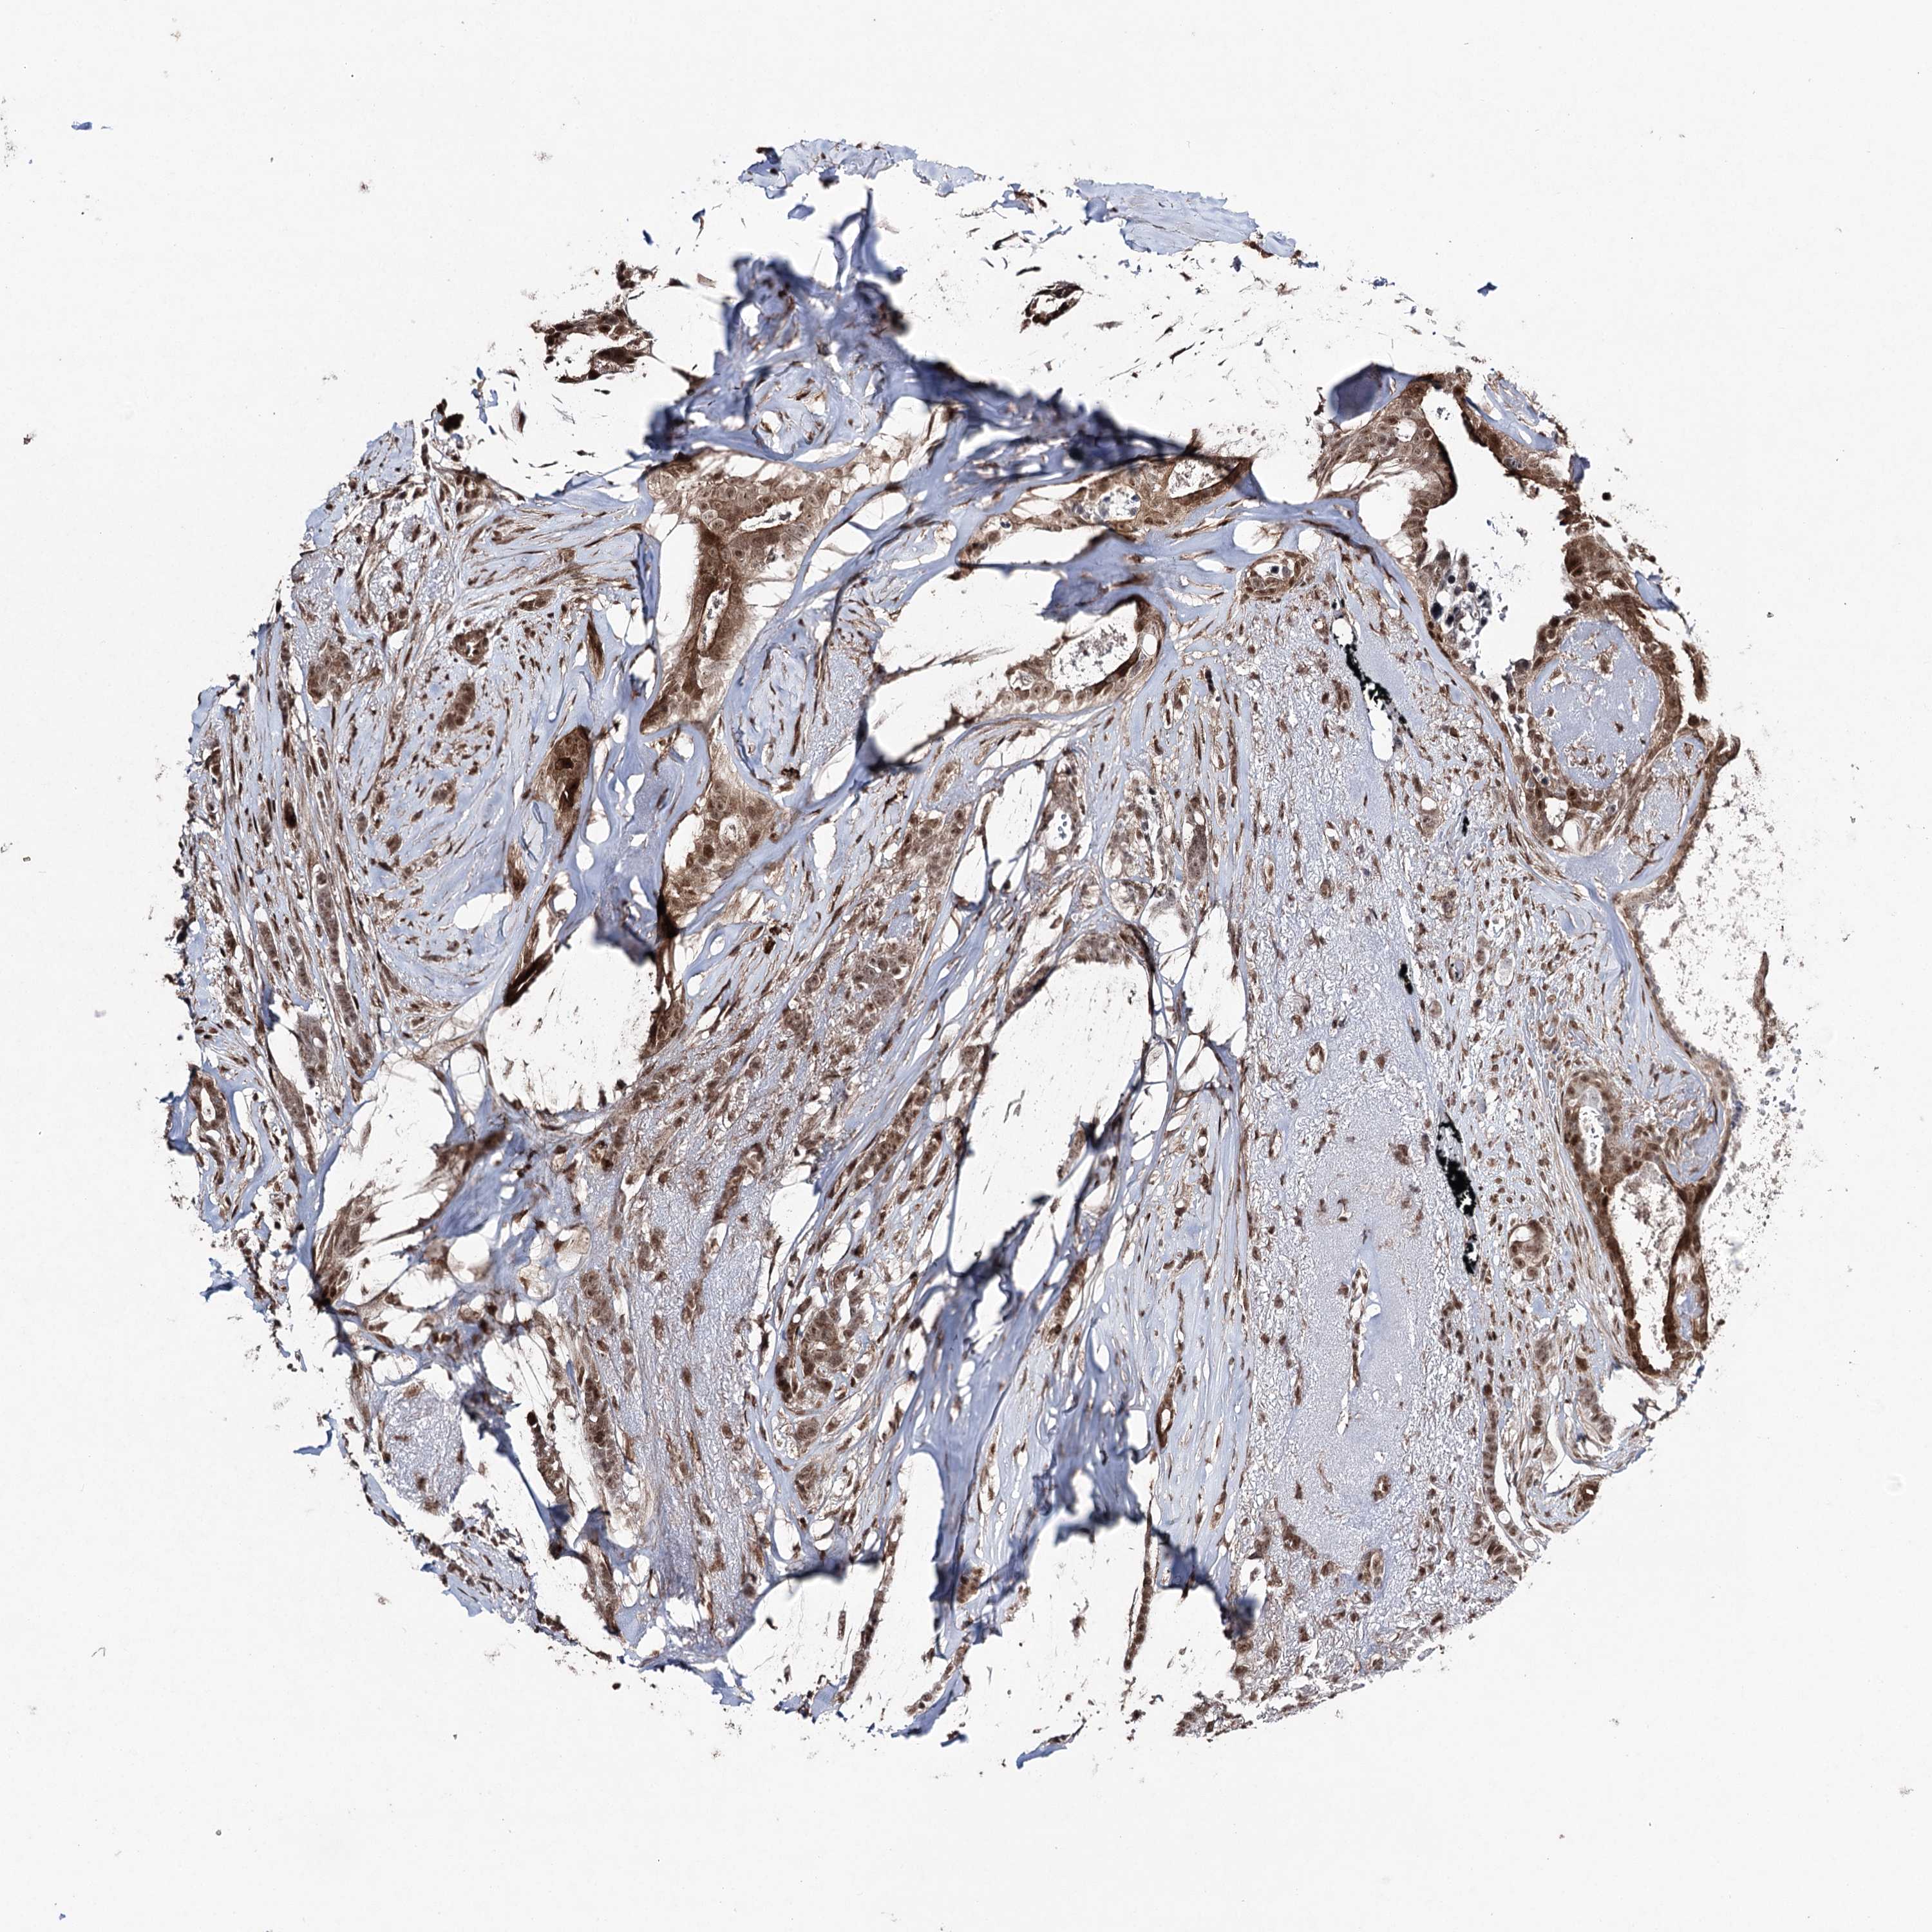

CANCER BREAST CANCER Show tissue menu

BRCA TCGA BRCA VALIDATION PROTEIN EXPRESSION

Breast cancer

Human cancer